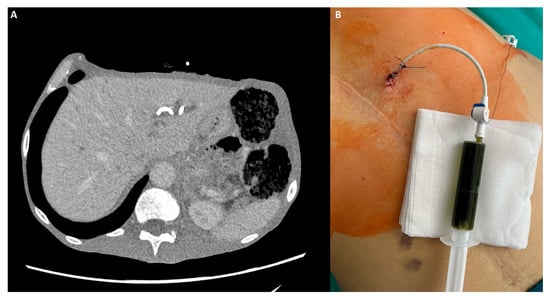

Background: After a failed endoscopic retrograde cholangiopancreatography (ERCP) for malignant biliary obstruction (MBO), second-line drainage is performed with endoscopic ultrasound-guided biliary drainage (EUS-BD) or percutaneous transhepatic biliary drainage (PTBD). We compared their effectiveness, safety, and short-term survival. Methods: We conducted a single-center retrospective cohort of 101 adults with MBO after they had experienced a failed ERCP (EUS-BD n = 37; PTBD n = 64). Allocation was non-randomized and driven by operational availability. Baseline laboratory tests (complete blood count, platelets, and C-reactive protein) and derived indices (neutrophil-to-lymphocyte ratio [NLR], platelet-to-lymphocyte ratio [PLR], lymphocyte-to-monocyte ratio [LMR], systemic immune-inflammation index [SII], systemic inflammation response index [SIRI], neutrophil-to-platelet score [NPS], and lymphocyte-to-CRP ratio [LCR]) were compared. Outcomes that were a technical success include: an early biochemical response (bilirubin reduction), complications (Clavien–Dindo), length of stay (LOS), and overall survival (OS). Between-group comparisons used the two-sided Mann–Whitney U test (continuous) and Fisher’s exact (binary) test. Survival was assessed by the Kaplan–Meier estimator using log-rank testing. To address later adoption of EUS-BD, we also estimated a restricted mean survival time of 180 days (RMST_0–180) with 95% confidence intervals (CIs). Results: Baseline inflammatory markers and composite indices were similar; baseline total bilirubin was higher in PTBD. The technical success was 100% in both groups. Early biochemical response was 86.5% after EUS-BD vs. 78.1% after PTBD (p = 0.43). Any complication occurred in 29.7% vs. 12.5% (p = 0.04); major complications (Clavien–Dindo ≥ III) occurred in 10.8% vs. 0% (p = 0.02), respectively; and the LOS did not differ (p = 0.21). OS favored EUS-BD (median 143 vs. 54 days and log-rank p = 0.012). RMST_0–180 was 111.1 days for EUS-BD vs. 71.4 days for PTBD (difference + 39.6 days; 95% CI 11.3–65.9). Conclusions: After a failed ERCP for MBO, EUS-BD and PTBD achieved universal technical success and similar early biochemical responses, but EUS-BD was associated with higher complication rates and a significantly longer six-month survival. These findings support the individualized selection balancing procedural risk with the anticipated survival benefit and highlight the need for prospective comparative studies. Full article

Show Figures

Figure 1